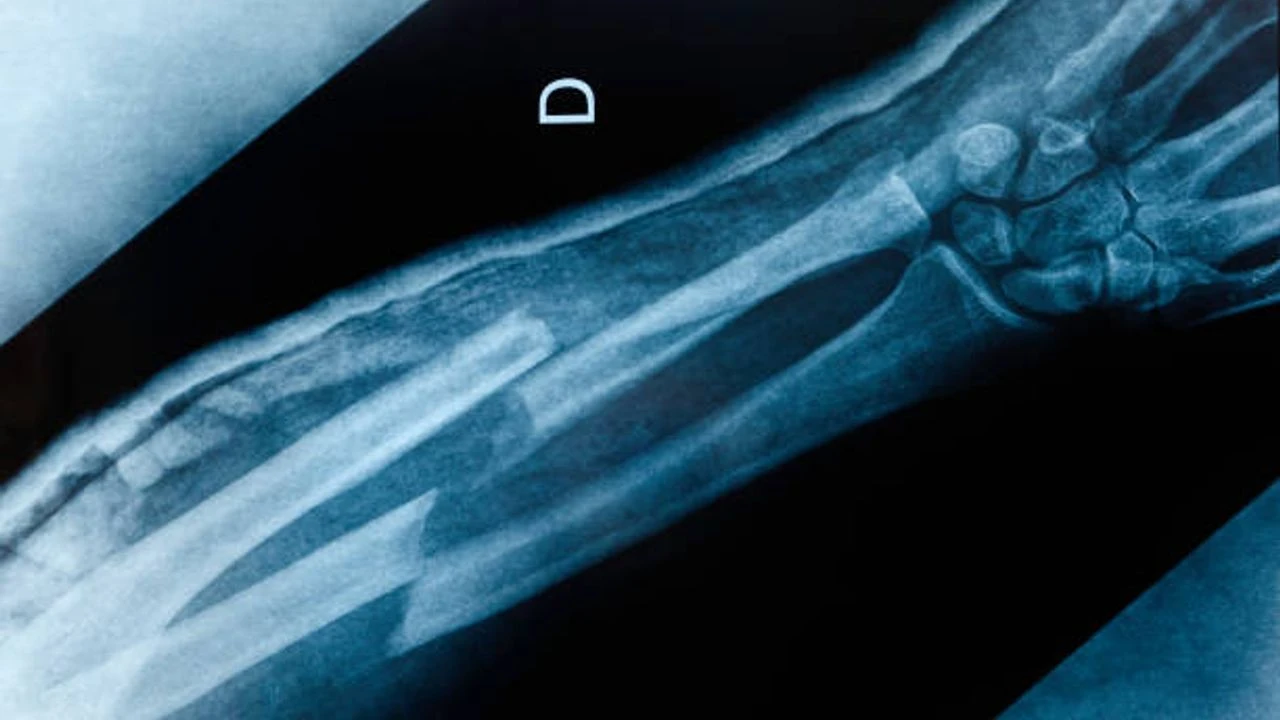

Çin'de bilim adamları, kırık kemik parçalarını yenileyen buluş niteliğinde yeni bir keşif gerçekleştirdi. Yapılan yeni çalışmayla ekipçe geliştirilen "Bone-02" isimli buluş, genel olarak haftalarca süren istirahat ve titanyum levha takılmasını gerektiren iskelet travmalarını tedavi etmeyi amaçlıyor.

Kemik yapıştırıcı yöntemi bir enjeksiyon şeklinde uygulanıyor. Öte yandan kemik parçalarını sadece 3 dakika içerisinde birbirine bağlıyor. Tasarlanan bu buluşun, tedavi yöntemi olarak istiridyelerden esinlenildiği belirtildi.

"Bone-02" öte yandan kemik onarıcı vücudumuz tarafından doğal olarak emiliyor. Böylelikle implantı çıkarmak için yeni bir ameliyat süreci tamamen ortadan kalkıyor.